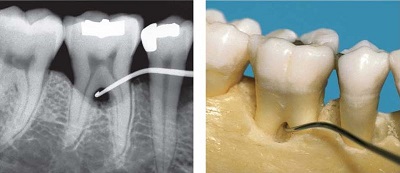

Ubytki kości w przestrzeniach międzykorzeniowych zębów trzonowych i przedtrzonowych. (Zmiany w furkacjach).

Ubytki kości w przestrzeniach międzykorzeniowych zębów trzonowych i przedtrzonowych

Ubytki tkanki kostnej w przestrzeni międzykorzeniowej są stosunkowo trudne do diagnostyki i do leczenia. Tylko 20% ubytków w przestrzeniach furkacji możemy rozpoznać na klasycznych zdjęciach RTG, na skanach tomografii komputerowej CBCT możemy rozpoznać już 84% zmian chorobowych w furkacjach. Badaniem klinicznym oceniamy kliniczne położenie przyczepu w wymiarze pionowym i w wymiarze poziomym. Zmiany I klasy w/g klasyfikacji Hampa kwalifikują się tylko do leczenia zachowawczego. Zmiany III klasy, wtedy gdy przestrzeń furkacyjna pod zębem otwarta jest po obu końcach najczęściej kwalifikują się do ekstrakcji zęba, lub zabiegu tunelizacji, jako tymczasowe, warunkowe rozwiązanie przed ostateczną ekstrakcją. Zmiany II klasy najczęściej kwalifikują się do leczenia chirurgicznego. Niekiedy leczenie ubytków kostnych połączone jest z radektomią, separacją korzeni, lub trisekcją zęba. Zawsze trzeba rozważyć leczenie chirurgiczne. Harrel i Nunn podają, że po roku od zabiegu chirurgicznego status periodontologiczny ulega pogorszeniu tylko u 1% pacjentów. W przypadku nie podjęcia leczenia chirurgicznego sytuacja miejscowa ulega pogorszenia nawet u 30% pacjentów. Jak wskazują powyższe wyniki leczenie chirurgiczne jest leczeniem z wyboru. Zabiegi na tkance kostnej, przy zmianach furkacyjnych należą do zabiegów sterowanej regeneracji tkanek. Stosując techniki mikrochirurgiczne, wykorzystujemy biomateriały jak kość wołowa FDBA, błony kolagenowe resorbowalne, PRP, CGF, czy białko matrycy szkliwa (Emdogain).